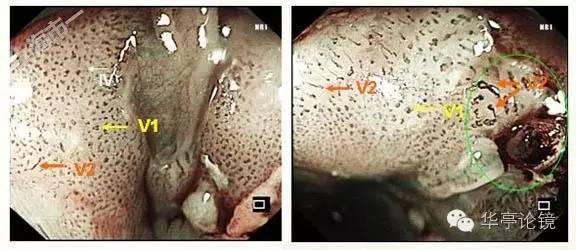

ME-NBI内镜:见多处病灶粘膜血管网异常,分支血管网缺失,局部背景着色阳性,IPCL呈IV-V1型改变为主(注:IV型: 出现扩张、迂曲、管径粗细不均或形态不规则改变中的2种或3种;V型:同时出现扩张、迂曲、管径粗细不均和形态不规则四种改变),局部见V2型改变(注:Ⅴ2型:在Ⅴ1型病变的基础上出现血管延长,原血管袢结构尚完整)。预测病变深度为m1(上皮层)为主,见下图。本文IPCL分型均按井上分型方法。

ME-NBI内镜:病变明显处分支血管网消失,IPCL呈IV-V1型改变为主,部分区域呈V2型改变。部分区域粘膜表层糜烂,表浅血管显露(绿色框内)。